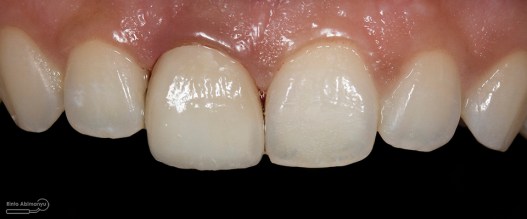

Kondisi awal saat pasien datang

Foto klinis setelah pemasangan crown